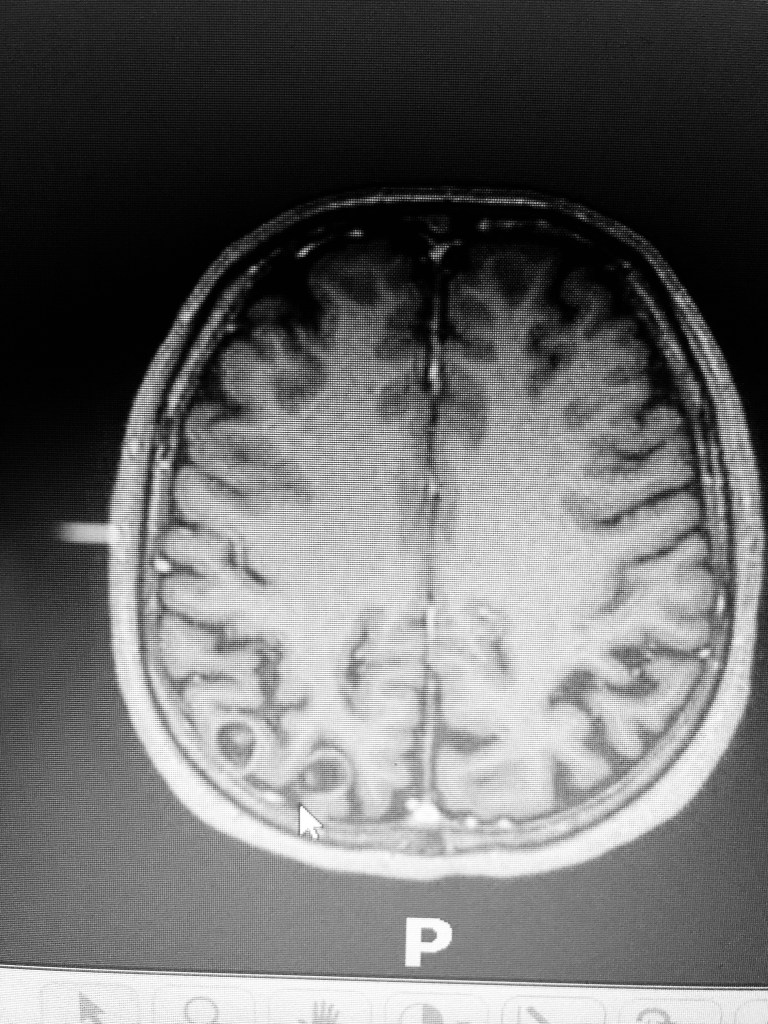

A seta mostra as lesões com escólex ( fotos 1 e 3) e o cistecerco racemoso em ventrículo (foto 2).